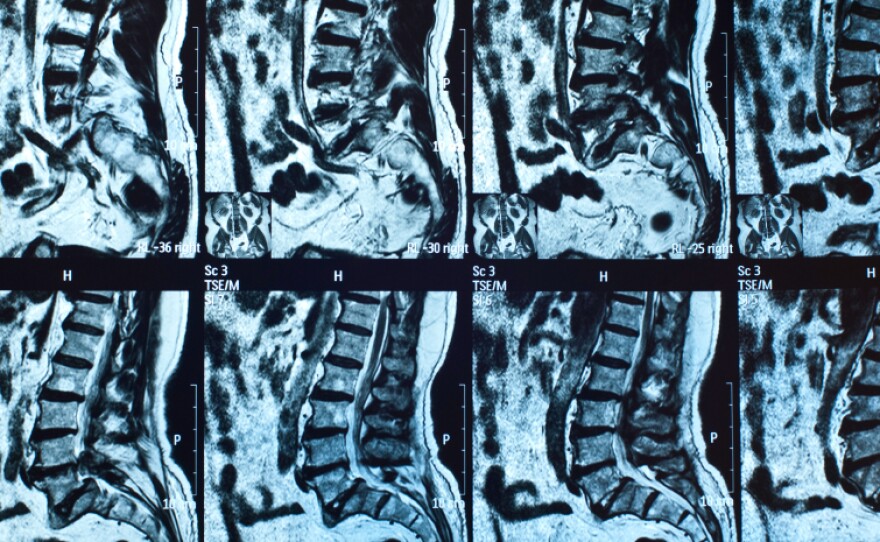

Spinal MRIs similar to these found infections that many patients hadn't realized they had.

Doctors at hospitals in Michigan did MRI scans of people who had been given tainted injections but didn't report symptoms of meningitis afterwards.

About 20 percent of the 172 people tested had suspicious-looking MRIs, and 17 ended up needing surgery to treat fungal infections in or around the spine.

This screening method isn't perfect: 17 percent of the patients screened had equivocal MRIs.